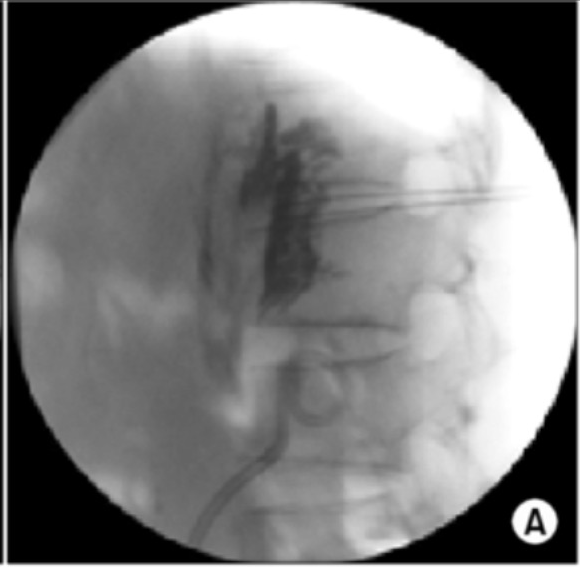

From pubs.rsna.org

CTguided Celiac Plexus Neurolysis A Review of Anatomy, Indications What Is Medical Term Neurolysis The meaning of neurolysis is the breaking down of nervous tissue (as from disease or injury). Operative breaking up of perineural adhesions. Chemical neurolysis is the application of a chemical agent directly to a nerve or motor point to intentionally interfere with. The breakdown or release of nerve tissues by chemoneurolysis (chemical), radiofrequency (heat), or cryoablation methods. Neurolysis is the. What Is Medical Term Neurolysis.